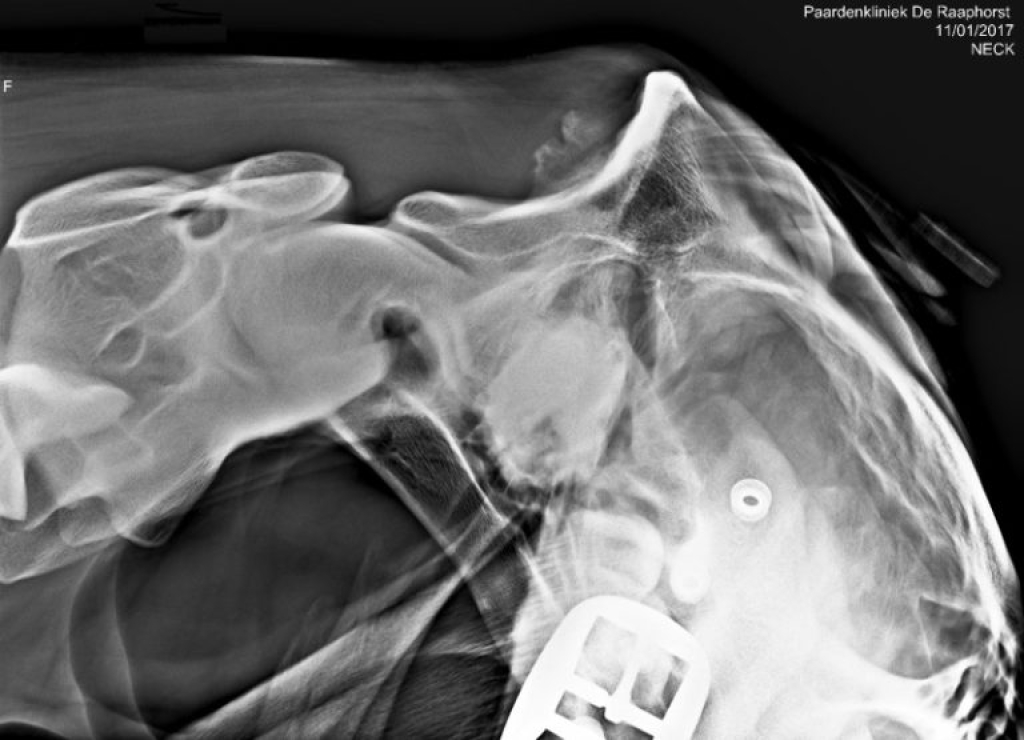

Echobeeld en röntgenfoto van het achterhoofd

Foto: Echobeeld en röntgenfoto van het achterhoofd

Het afvoelen van het gebied van de aanhechting van het ligamentum nuchae leidt niet altijd tot een duidelijke pijnreactie. Om de diagnose te kunnen stellen is het daarom nodig om het gebied in beeld te brengen met röntgenfoto’s en een echo. Omdat veranderingen die we waarnemen met röntgen en echo niet altijd in relatie staan tot klinische problemen kunnen de beelden nooit los gezien worden van de klachten bij het paard. Belangrijk hierbij is de mate van botbeschadiging, botactiviteit en of ook de aanhechting van de semispinalispees betrokken is. Zo zien we veel paarden met een onregelmatige botbelijning van het achterhoofd, zonder dat deze klachten hoeven te hebben.